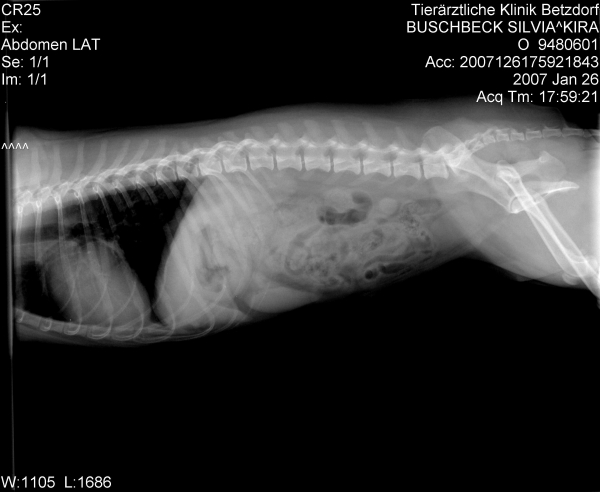

Da Kira aber inzwischen beim TA fürchterlich unter Stress steht, hat man beschlossen, zumindest schon einmal die Röntgenaufnahme des Herzens zu machen.

Die Aufnahme gefiel dem Chef nun weniger und er hat es möglich gemacht, dass Kira gestern abend dann doch noch die Ultraschalluntersuchung bekam.

Kira's Herz ist sehr vergrößert Konfus .

Zum Vergleich: ein normales Herz liegt auf ca. 2 Brustwirbeln auf, Kira's Herz beansprucht 4,5 Brustwirbel und drückt bereits die Luftröhre nach oben Geschockt

Eine Mitralklappeninsuffiziens (geringgradig), eine Pulmonalklappeninsuffizienz (ebenfalls geringgradig) und laut Diagnosebericht für meinen TA eine beginnende HCM. Hier muß ich noch einmal nachfragen, was genau damit gemeint ist.

Die Werte des Herzens sind ansonsten in Ordnung, Durchblutung, Durchflußgeschwindigkeit und Kontraktionen sind alle im Normbereich.

Sie bekommt vorerst keinerlei Medikamente fürs Herz, lediglich ein jährlicher großer CheckUp mit Herzdiagnostik wird künftig gemacht.

Die "undichten" Klappen können - müssen aber nicht - irgendwann einmal Probleme verursachen - im Augenblick tun sie es nicht.

@Christa: Ja, der Doc sagt auch, dass ein ETWAS vergrößertes Herz durchaus die Regel sei. Ihres aber ist fast doppelt so groß wie normal und zeigt zudem eine dicke Herzmuskelwand - eben die beginnende HCM. Zudem ist das Herz ja einseitig noch mal etwas vergrößert, also ungleichmäßig. Was daraus wird....man wird sehen.